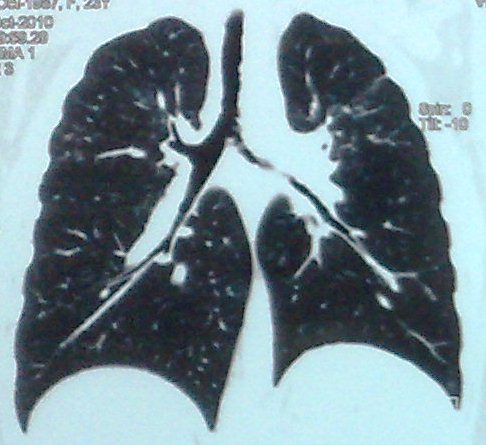

- გულმკერდის კტ სტენტირებამდე (Coronal) 8 თვით ადრე